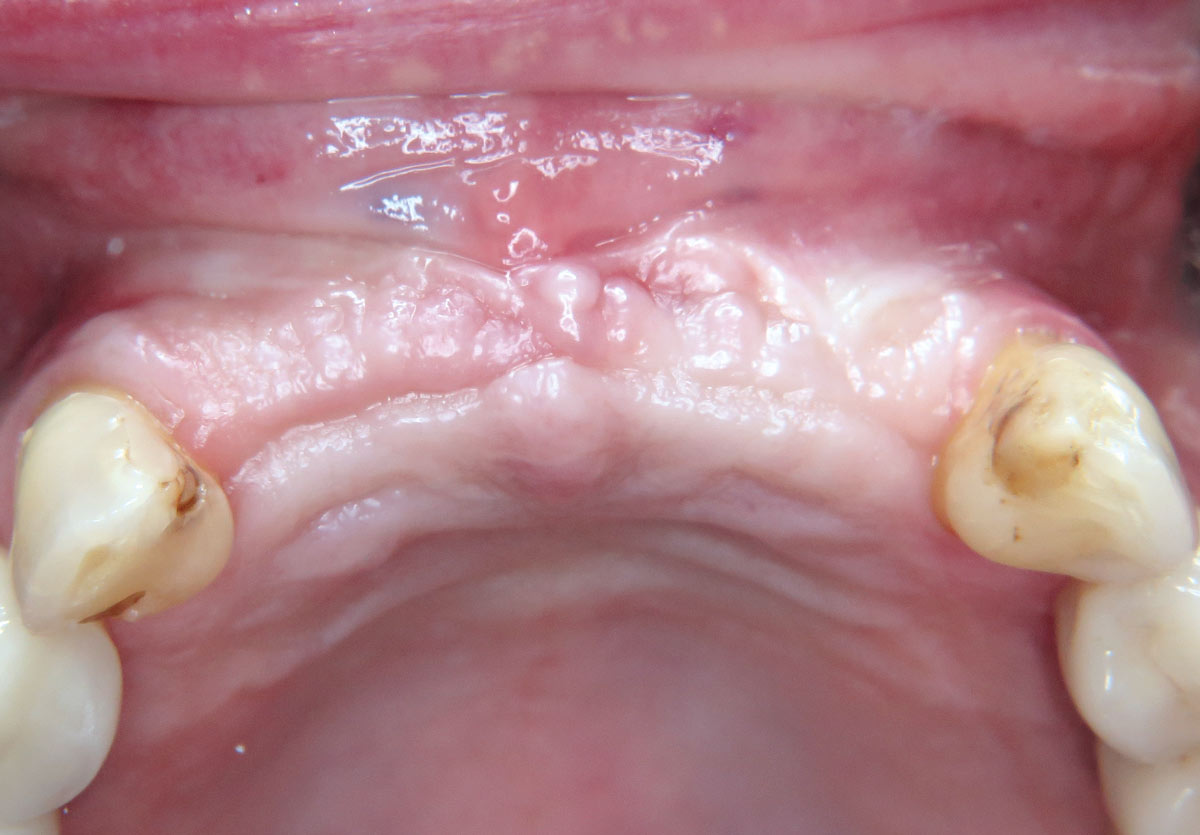

01 / 22 - Initial clinical situation – missing bonein regio 11, 12, 21, 22 and scarred soft tissue